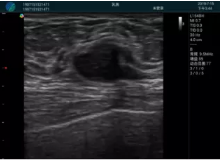

可視化甲狀腺穿刺引導(dǎo)

頸動(dòng)脈血流充盈飽滿,無外溢

肝內(nèi)血管顯示清晰,血流敏感無外溢

病例二:

甲狀腺囊性結(jié)節(jié),囊壁鈣化,透聲好

甲狀腺囊性占位